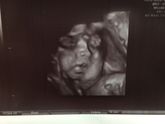

Совсем недавно не было живота и я только догадывалась о том что у меня в животе кто-то есть, а щас осознаю что ещё чуть-чуть и у меня будет маленькое щекастое счастье, которое я буду любить больше жизни.